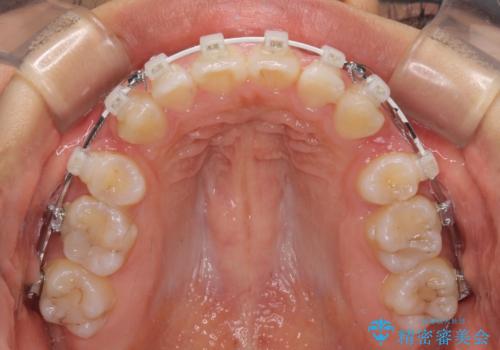

上顎抜歯のみでは奥歯の咬み合わせを改善することが困難であったため、途中で下顎小臼歯も抜歯をしました。

抜歯のタイミングが遅れると治療期間が長期化するため、速やかに抜歯の判断をし、2年強の期間で治療を終えることができました。